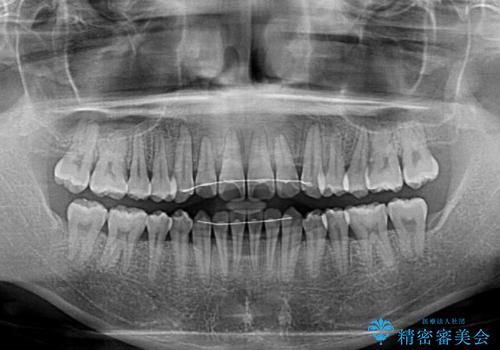

前歯のクロスバイト インビザラインによる矯正治療

- 上下のクロスバイトと前歯のデコボコを気にして来院された患者様です。

インビザラインを用い、IPR(歯と歯の間を削る)と歯列全体を拡大させることで、歯並びを整えていくこととしました。

上下ともに歯列全体を後方に移動させるため、上下の親知らずを抜歯することとしました。